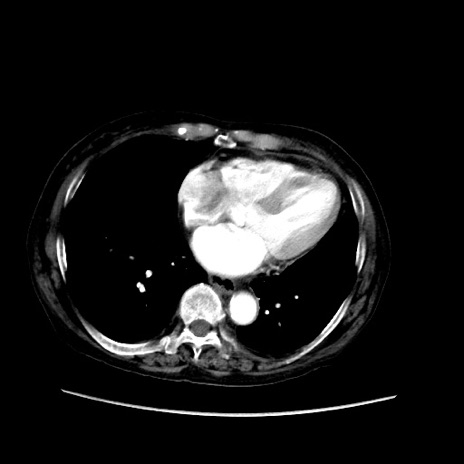

冠状断像